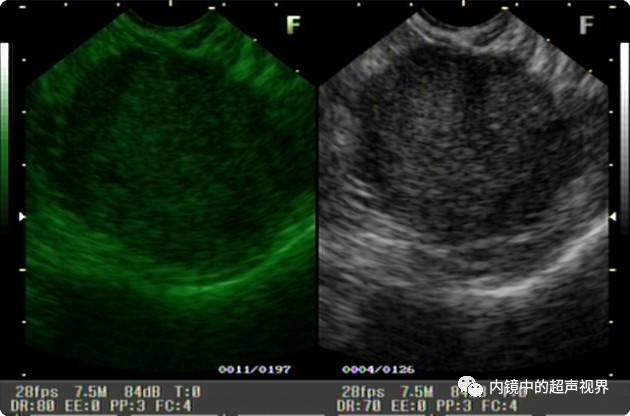

再来一张间质瘤的图片,也是DR30和80的对比。

有没人觉得,这个间质瘤的图片跟前面两个病灶不太一样,似乎感觉高DR模式看起来更舒服,那是因为,间质瘤为低回声,它周围的软组织为高回声,本身就能形成良好的对比,无需降低DR,而高DR模式更显细腻。

说到这里有没有人想到超声造影的那种模式啊?一样的双屏对比,一样的黑。那种模式是不是降低DR调来的,我没有做过超声造影,只是这样猜测,请大咖前来指导。

间质瘤